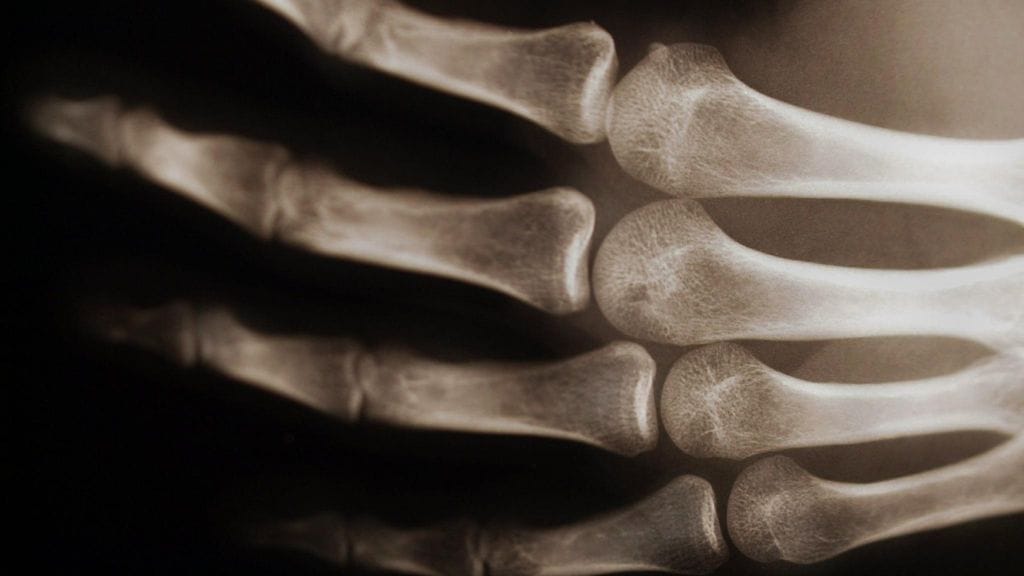

Osteoporoosia kutsutaan usein näkymättömäksi tai hiljaiseksi sairaudeksi, koska luukato tapahtuu vähitellen ilman näkyviä merkkejä tai oireita. Lopulta luustosta voi tulla niin heikko ja hauras, että pienikin kolautus, äkillinen liike, putoaminen tai kaatuminen seisomakorkeudelta voi aiheuttaa luun murtuman.